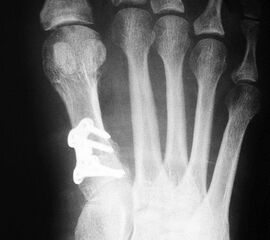

Abbildung 2

• Kleines Fußinstrumentarium.

• Herstellerspezifisches Plattensieb und Osteosynthesen für ergänzende Korrekturen (z.B. Axomed Pedus-O® (Abb. 2.) -Axomed GmbH, Heinrich-von-Stephan-Str. 5c, 79100 Freiburg; Darco MFS® - DARCO GmbH & Co. KG, Gewerbegebiet 18, D82339 Raisting; Merete® - Merete Medical GmbH, Alt-Lankwitz 102, 12247 Berlin usw.).